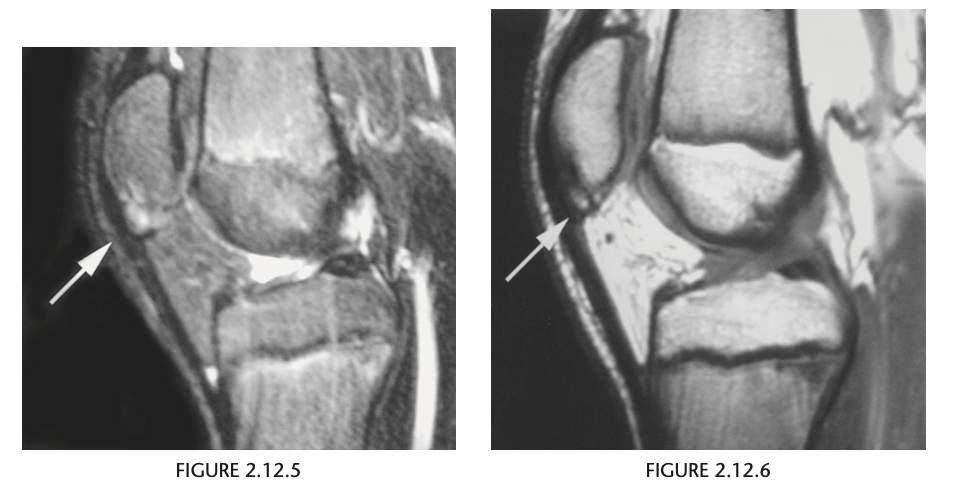

Figure 2.12.4 is a coned-down,

lateral knee radiograph of a 13-year-old athlete

with anterior knee pain and shows fragmentation

of the inferior pole of the patella (arrow). The sagit-

tal T2-weighted MR image (Fig. 2.12.5) confirms the fragmentation of the patella and shows prepatel-

lar edema and edema within the proximal patellar

tendon (arrow). The sagittal T1-weighted MR image

(Fig. 2.12.6) shows the fragmentation of the patella

that is characteristic of this disorder (arrow).